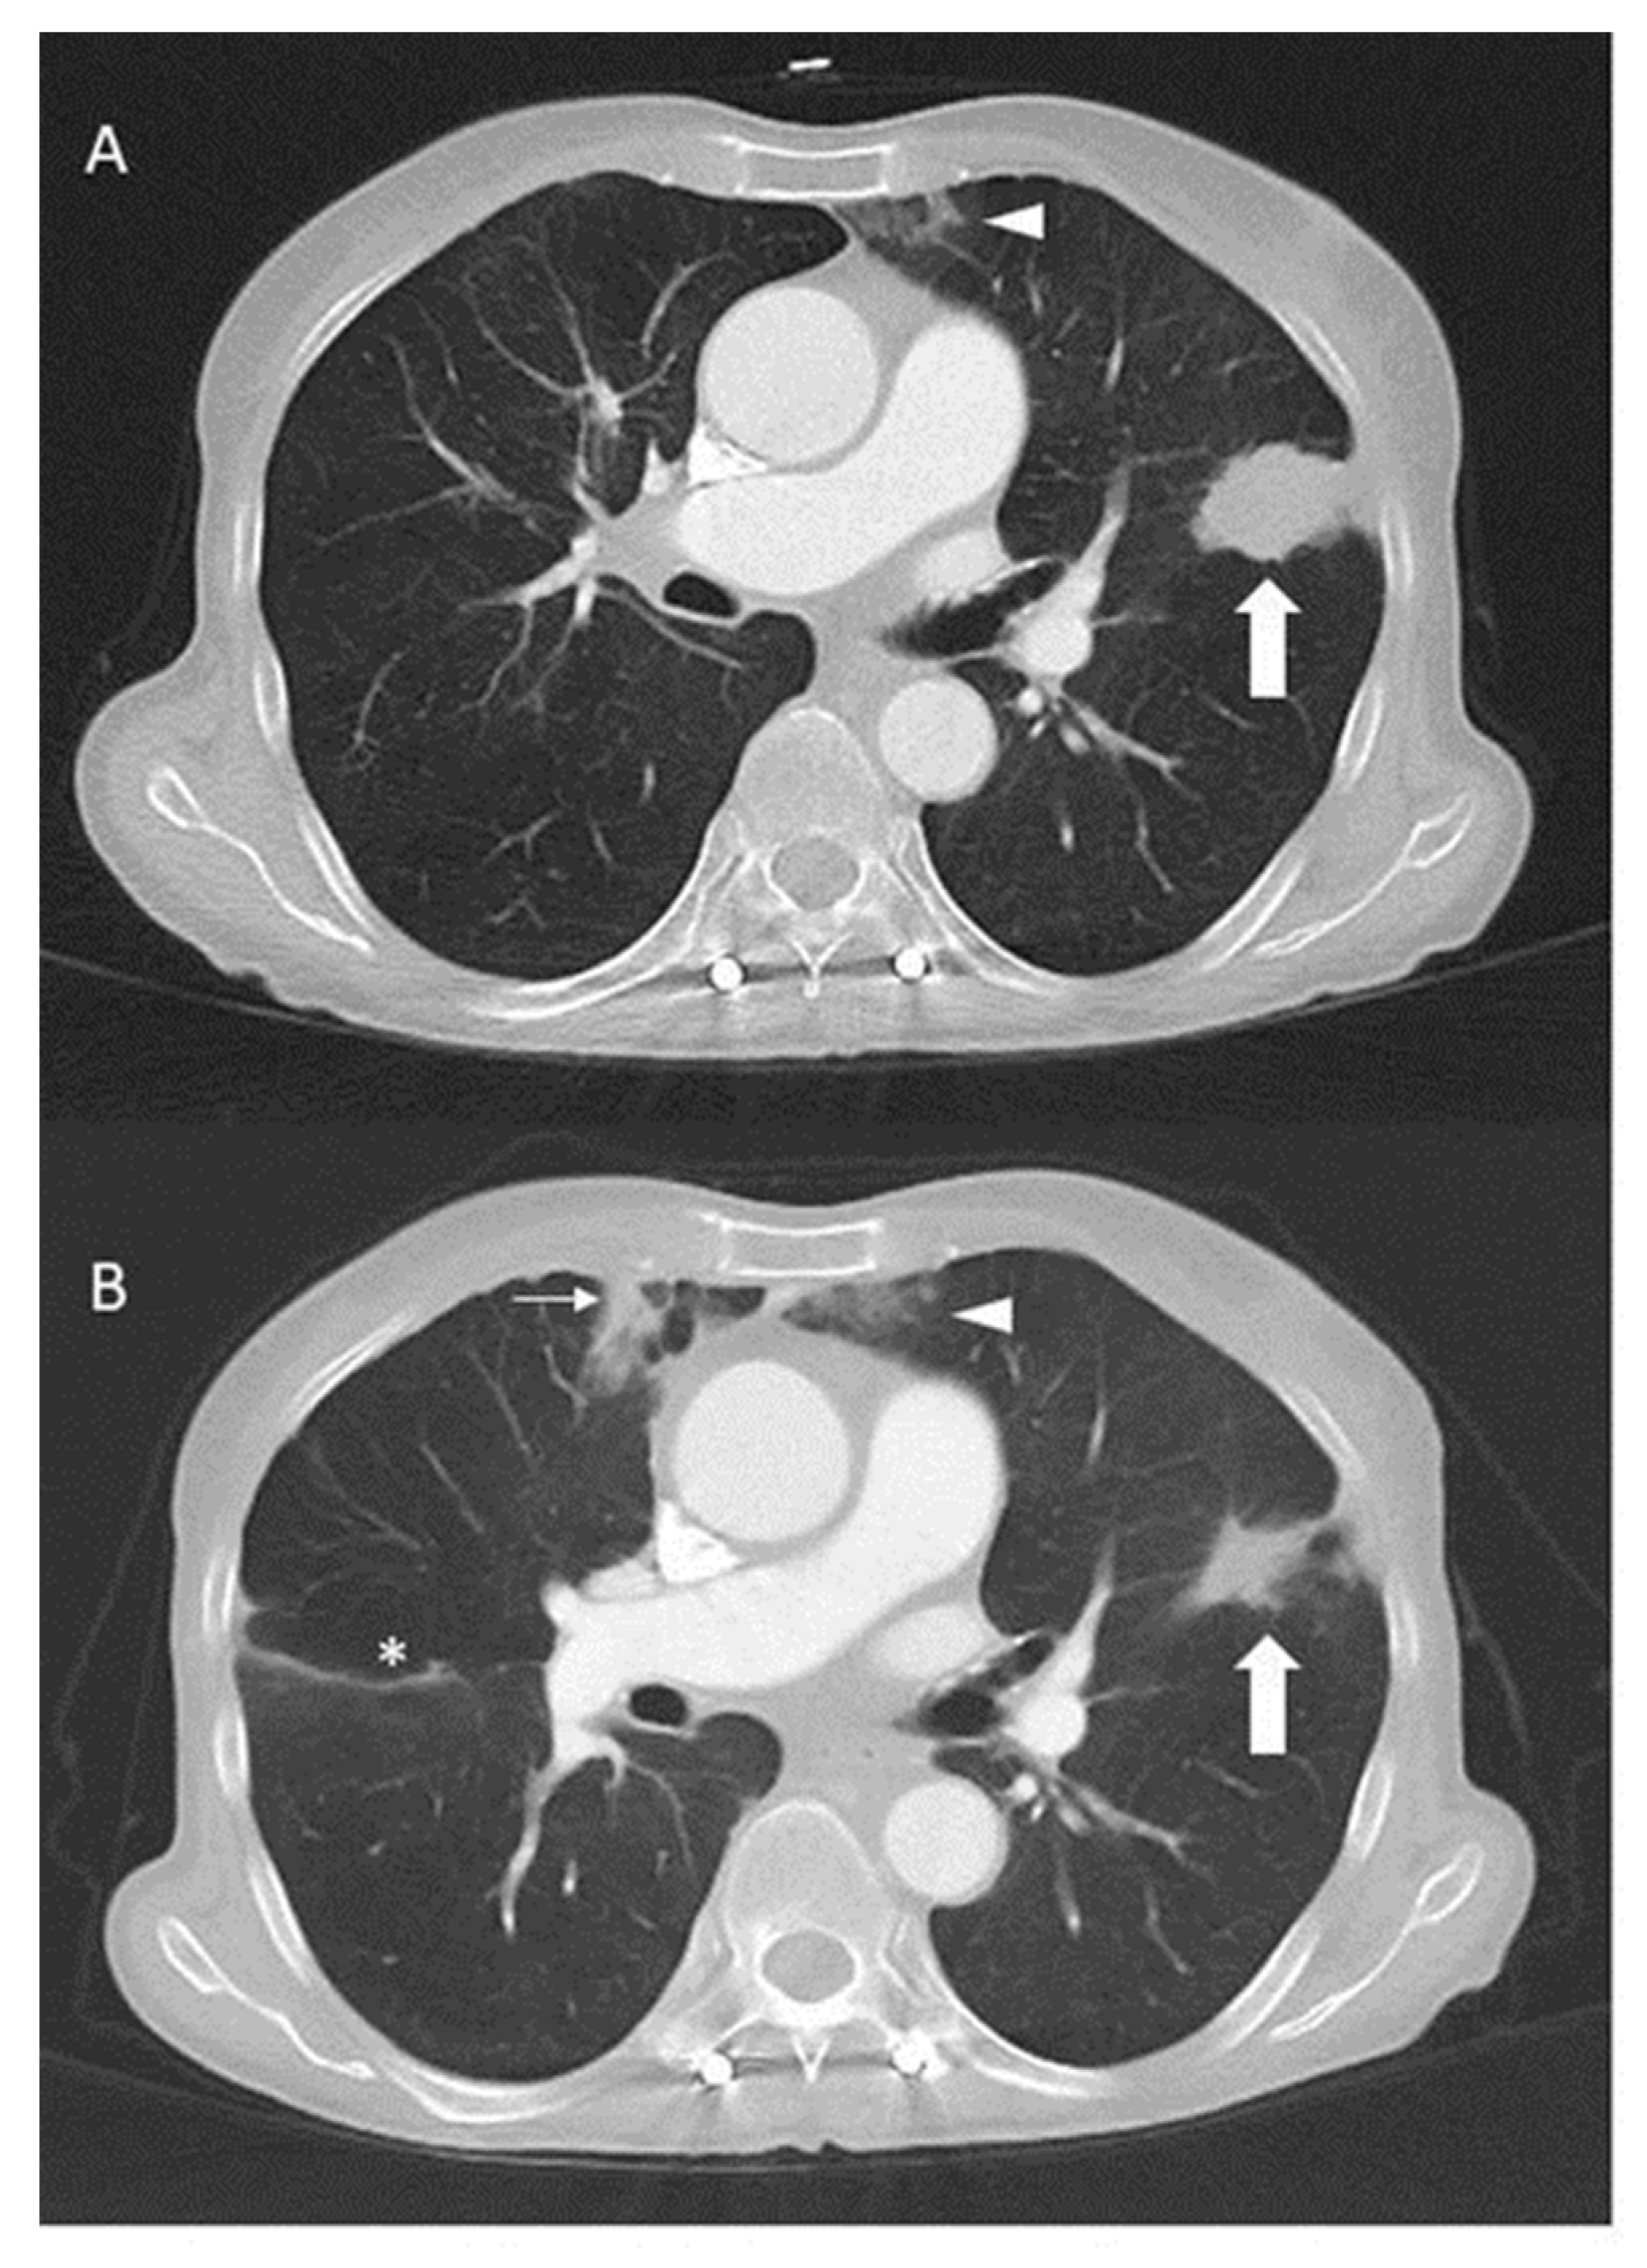

2. Case Presentation